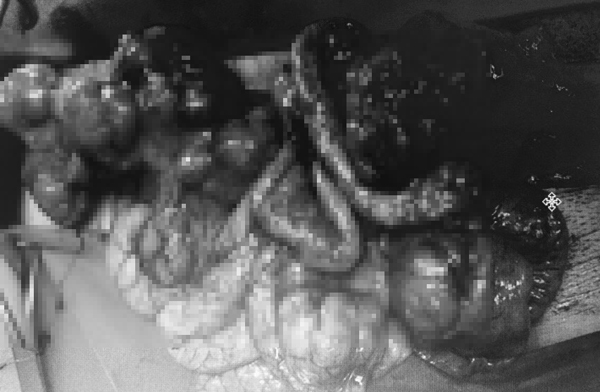

| Gần 100 khối u lớn nhỏ được lấy ra |

Ca mổ kéo dài hơn 6 giờ đồng hồ. Kíp mổ đã cắt bỏ một phần dạ dày kèm lách, cắt nhiều đoạn ruột bị u xâm lấn nguy cơ gây tắc ruột, lấy tối đa u trong ổ bụng với tổng số lên tới gần 100 khối u. Trong đó nhiều khối u đã bị vỡ, gây chảy máu.